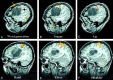

Fig 1.

Sagittal SPGR images of a left frontal astrocytoma centered in the left subcentral gyrus and IFG. The tumor displaces the pars opercularis of the left IFG superiorly and anteriorly, as demarcated by the displaced inferior frontal sulcus (arrows). The lower central sulcus (CS), precentral sulcus (Pre-CS), precentral gyrus, and postcentral gyrus are displaced superiorly and posteriorly.